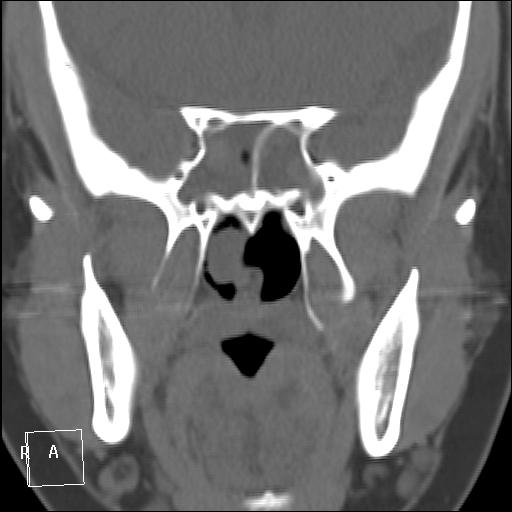

КТ ППН и носоглотки. Девушка 21 года. Полипозный риносинусит.

Госпитализирована для оперативного лечения. Удалены полипы носа. Вторым этапом планируется гайморотомия. Во время операции - подозрение на образование носоглотки. Сохраняется затруднение носового дыхания. Направлена на КТ. Категорически отказалась от контрастировния (лекарственная полиаллергия, боится).

Полип в носоглотке справа. Нарушена пневматизация придаточных пазух носа кроме левой решётчатой. В левой гайморовой на дне неясно что…

На дне гайморовой - полип, в носоглотке немаленький хоанальный полип. Там всё в полипах, а они и фиброзные бывают, и ангиофибромы, и ангиоаденомы... Вот и плотность разная.

Ну, как-то все в одну кучу - и полипы, и ангиофибромы. При ангиофиброме, например, околоносовые пазухи свободны. А гиперденсность более характерна для грибкового поражения (аспергилеза), в том числе и "севшим" на пломбировочный материал.

На операции визуально полипы аденоматозного типа. Какие будут гистологически после гайморотомии - сейчас трудно сказать. Если б гиперденсность была только по нижней стенке верхнечелюстной пазухи, тогда вариант с аспергиллезом на пломбировочном материале, на мой взгляд, был бы более вероятен. У девушки участки гиперденсности по всем стенкам верхнечелюстных пазух, в основной пазухе, совсем чуть - в решетчатом лабиринте слева, без костной деструкции. Без посева и гистологии - только гадать)). В носовой полости признаков грибкового поражения ЛОРы не отмечают. Но Вы правы, может иметь место изолированное поражение синусов.